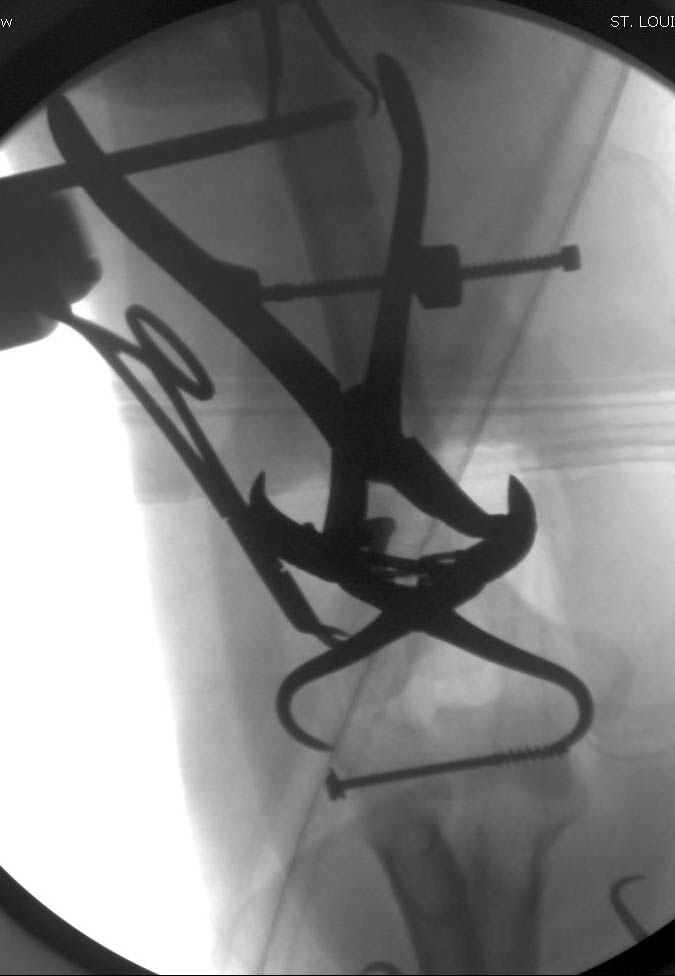

Примерный случай, только перелом был открытый, в задне-медиальной стороне рана около 2 см по характеру "изнутри кнаружи", неврологический статус со слабостью сгибания мизинца, также слабая абдукция и аддукция указательного пальца и сгибания в кисти.

Больному сделали обработку и наложили временный аппарат внешной фиксации плечо-предплечье.

На шестой день сделали открытую репозицию чрезлоктевым доступом двумя locking plate, локтевой нерв был ушибленным, после операции положительная динамика в Flexor Carpi Ulnaris. Фиксацию локтевого отростка произвели tension band technique с дополнительным шурупом.

Этапы операции на снимках....

Джолдас Кульджанов

Djoldas Kuldjanov, MD

Department of Orthopedic Surgery

St. Louis University Medical Center